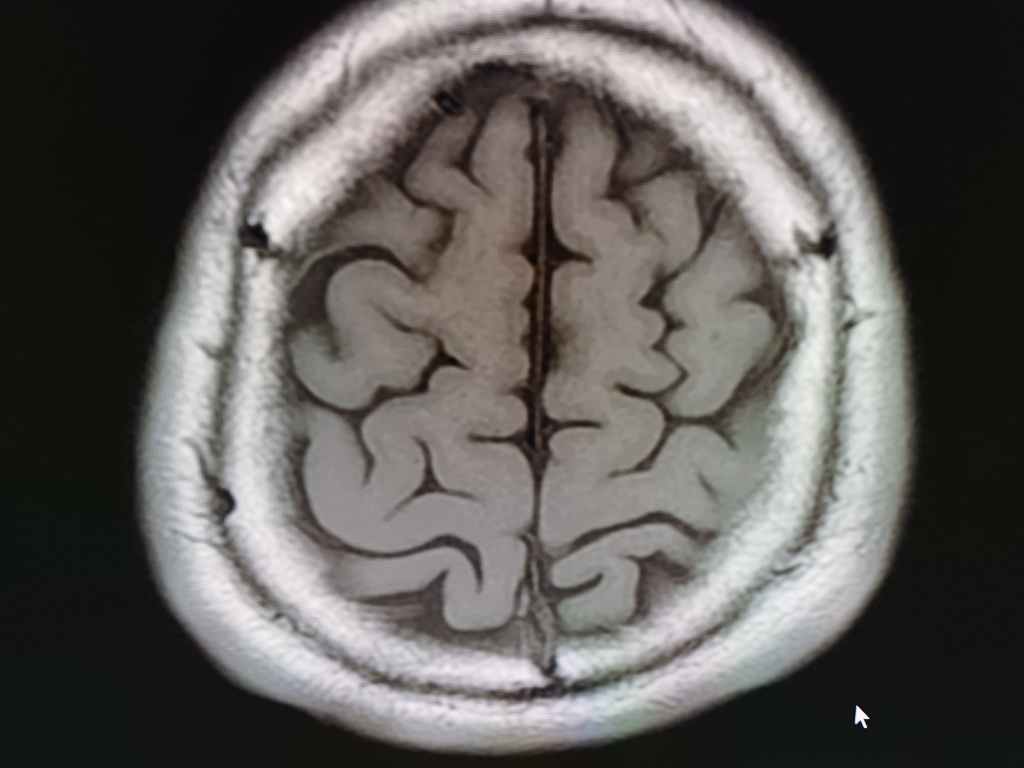

뇌 mri mra를 찍었는데 전문가분들의 고견을 구합니다.

안녕하세요.불편한 어지러움이 한달이상 지속되어 혹뇌쪽 이상이 아닌가 싶어 오늘급하게 mri mra를 촬영하고 왔습니다.결과를 바로 확인할수 있는줄 알았으나 일주일정도 기다려야 판독이 나온다하여 급한 마음에 사진 몇장 첨부하오니 답변해주시면 감사하겠습니다!!

• 2번 째 사진

업로드해주신 MRI 및 MRA 영상은 특별히 이상한 소견이 보이지 않습니다

뇌실질에 이상소견 없으며 뇌혈관이 막여있거나 좁아진 부분도 보이지 않습니다

현재 올려주신 사진만으로는 아주 큰 병변 이 있어 보이지는 않으나, MRI의 경우 연속된 단면을 모두 봐야 병변을 정확히 확인할 수 있으므로 해당 사진들만으로는 병변의 유무를 모두 다 확인 불가능합니다. 추후 판독을 기다려 보시기 바랍니다.